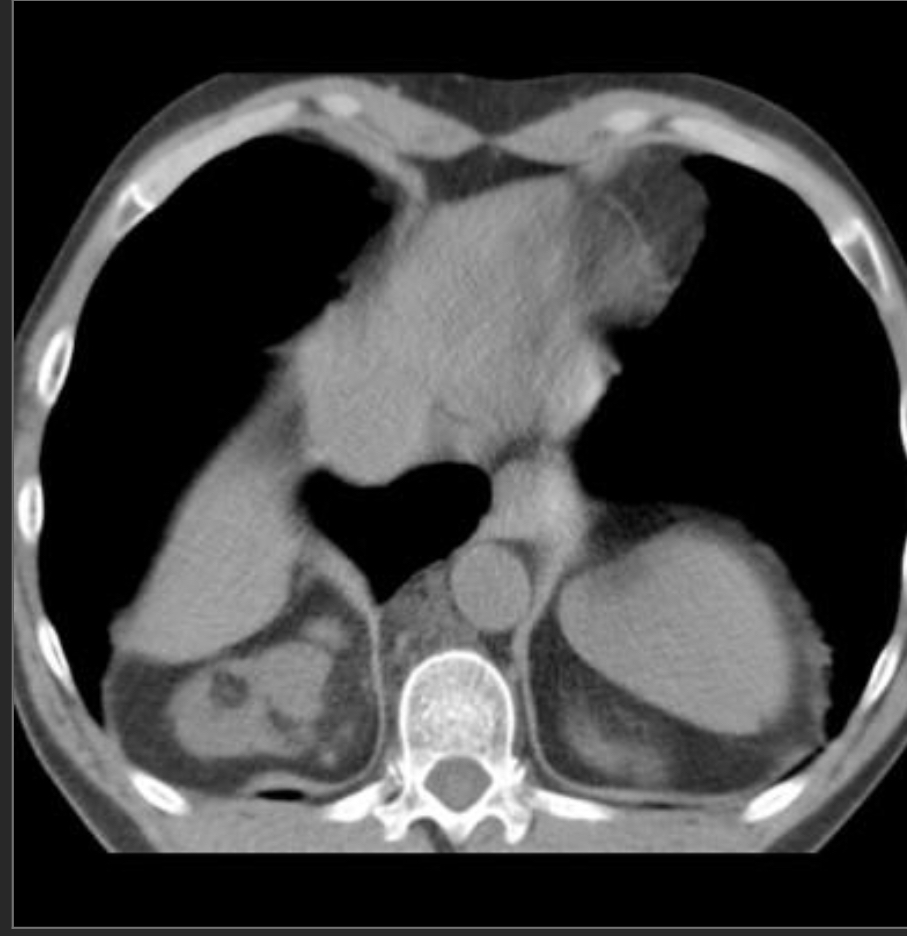

hypoplastic right lung with ipsilateral mediastinal shift and vertical vein (PAPVR of a portion or all of the right lung)

Scimitar Syndrome

Could also px as: bilobed right lung with a hyparterial right main and upper lobe bronchus

If systemic arteries from the abdomen are found to supply a portion of the lung, the resultant “complete” entity is also known as the scimitar syndrome.

**hyparterial bronchus–bronchus is below the PA (normal on the L but not the R)